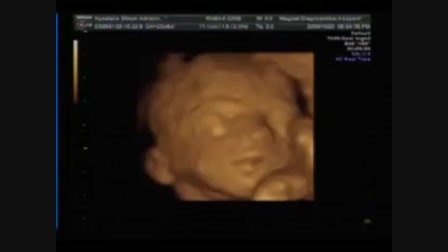

Vanda a cserkeszőlői strandon (2011-06-21)